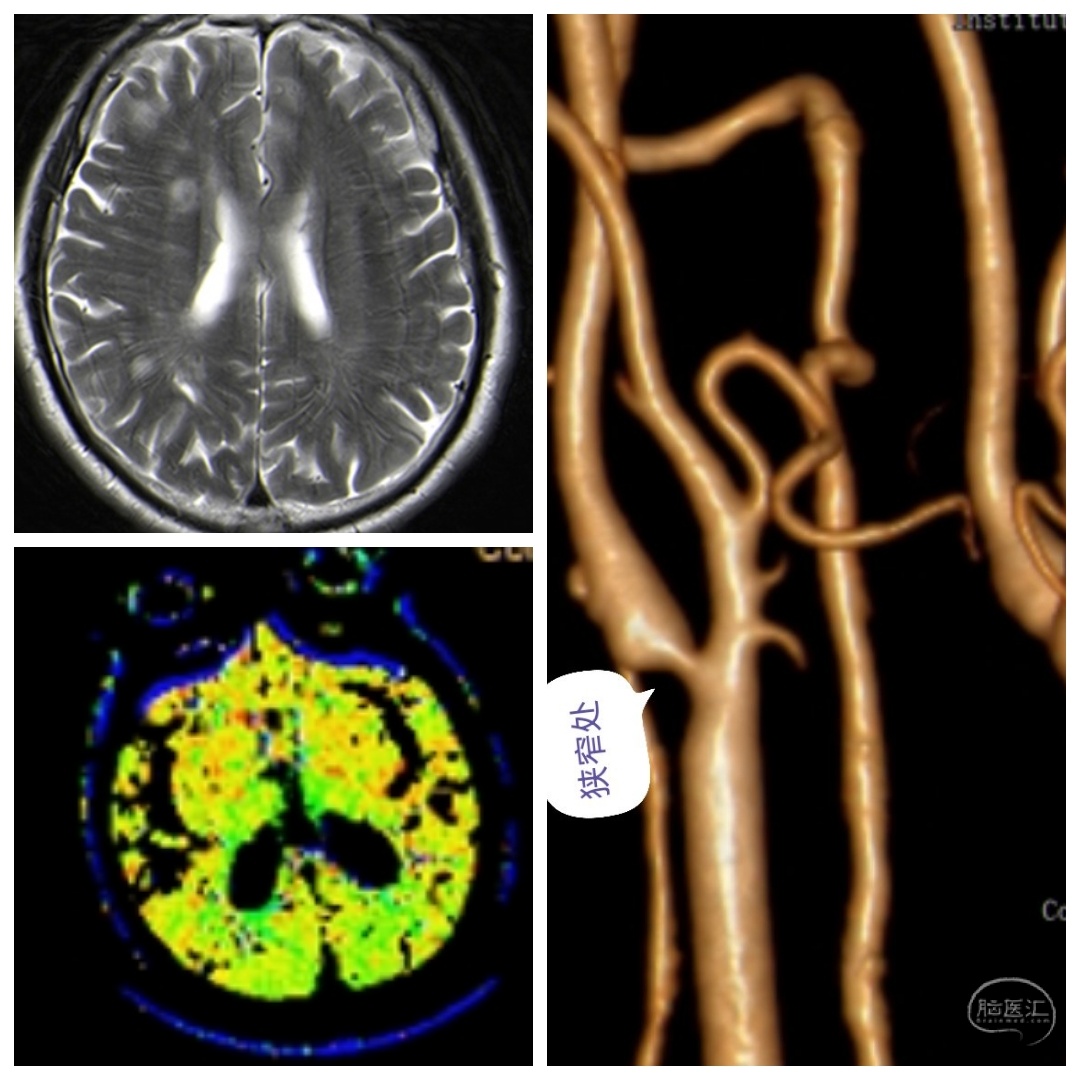

病例三、颈动脉狭窄(CEA内膜剥脱术)

刘某某,男性,70岁,因“反复头晕半年,加重一个月”入院。

查体:神志清,言语正常,肢体活动可,左侧肢体稍乏力。

MR提示右侧多发腔隙性脑梗塞,CTA提示右侧颈内动脉起始处狭窄90%。

术中暴露充分颈动脉,切开颈内动脉后可见粥样斑块,切除斑块,缝合,一气呵成!天下武功,唯快不破。。。

术后随访

CTA提示右侧颈内动脉狭窄消失,患者头晕症状消失